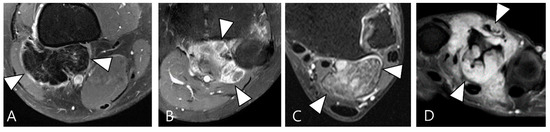

2.3. Morphological Findings for D-TSGCT

2.4. Relationship to Adjacent Structures of D-TSGCT

2.5. Advanced MRI Sequences for D-TSGCT